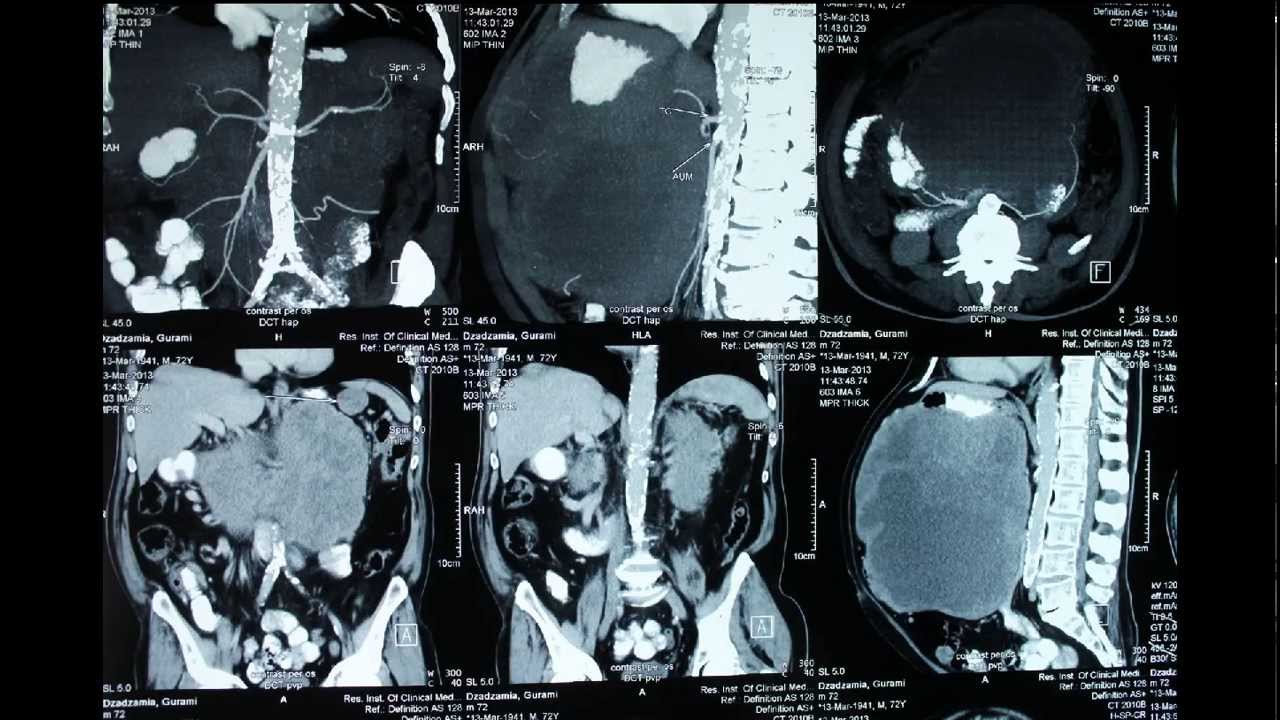

This video describes surgical case of 72 year old man with giant retroperitoneal abdominal tumor. It consisted from liquid and tissue parts. First liquid was evacuated and then all abdominal mass was resected radically.